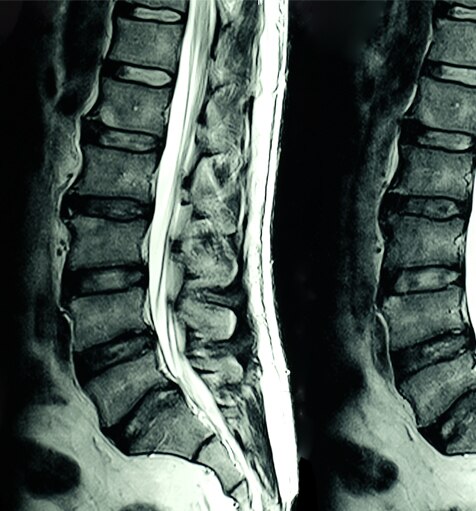

L’MRI (risonanza magnetica per immagini) è una tecnologia di scansione non invasiva che produce immagini del corpo elaborate in sezione trasversale. Viene utilizzata in diversi ambiti medici, tra cui: diagnosi muscoloscheletriche, gastrointestinali, oncologiche, cardiovascolari e neuroimaging. La scansione MRI è in grado di differenziare le strutture dei tessuti molli su qualsiasi piano, rivelandosi un prezioso strumento diagnostico.

Gli scanner per MRI generano un forte campo magnetico che, utilizzato in combinazione con la corrente a radiofrequenza, stimola molecole specifiche del corpo.

Il comportamento di tali molecole consente di generare un’immagine tridimensionale dei tessuti corporei. Di seguito sono mostrate alcune immagini ottenute con MRI: